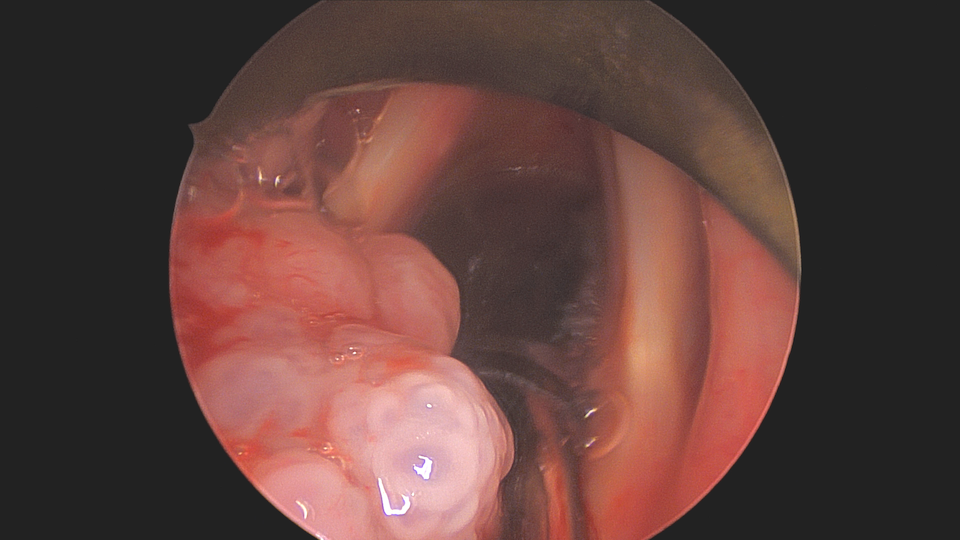

papilloma on the uvula, which is part of the soft palate

Papilloma on the uvula, which is part of the soft palate. Technically, this location is part of the throat (oropharynx).

Papilloma is a non-cancerous growth caused by the human papilloma virus (HPV) and may be present in the throat, oral cavity, larynx (voice box), or nasal passages. A papilloma may progress to p16+ squamous cell carcinoma, though this is statistically an uncommon event, and when it does occur, almost always occurs in the tonsil or base of tongue and only with certain high-risk strains of HPV (most commonly types 16 or 18).

Diagnosis of a papilloma in the mouth, nose, or throat may be highly suspected based on its appearance, but definitive diagnosis is with a biopsy and pathologic examination. Often, a small papilloma that is found to be benign with biopsy needs no other treatment.